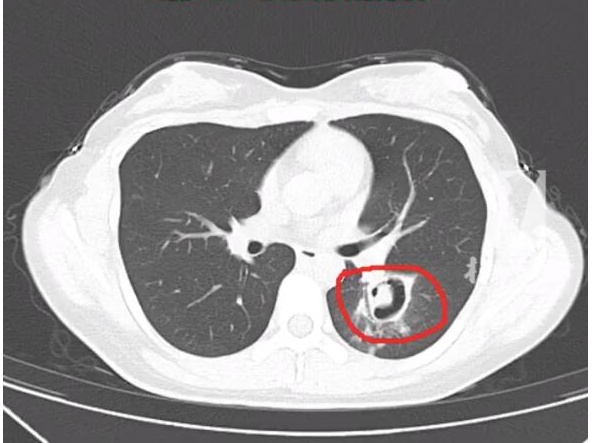

一个星期前,在杭州居住的一位00后的王小姐(化名)开始出现咳嗽、乏力和高烧,体温最高达到了40度。情况严重,王小姐被朋友送至附近的杭州师范大学附属医院。通过一系列检查,医生在肺部CT上发现,王小姐的肺部有多个“小树芽”,疑似是霉菌性肺炎。王小姐透露,一个月前她发现家中衣橱有霉点,进行清理时没有做好防护措施,吸入了大量扬起的杂质和灰尘。随后出现了阵发性咳嗽,虽然轻微但被忽视了。在了解情况后,医生给她做了纤维支气管镜检查,发现气道壁上有大量白色霉菌斑点,化验确认为曲霉菌。医生提醒大家,现在正是南方气候回暖时节,雨水不断,空气湿润成为霉菌生长的理想条件。除了可能导致肺部感染外,霉菌还可能引发口腔、皮肤、泌尿系统、胃肠道等感染,甚至全身感染。过敏体质的人吸入霉菌后可能产生过敏反应。建议在打扫卫生过程中戴口罩、穿长袖长裤,打扫完毕后尽快换衣服。为防止霉菌生长,可挂除湿盒或除湿袋,使用除湿机或空调,保持室内湿度在40%-50%之间。另外,不要储存过多食物,发霉的食物应立即丢弃,不要食用隔夜食物。同时,尽量减少室内绿植种植,防止土壤中霉菌滋生。除霉的同时也要注意防止霉菌滋生。想要杜绝霉菌滋生,去除霉斑只是暂时措施,预防才是根本之道。通常情况下,霉菌是肉眼不可见的。要是家中出现大面积霉斑,那说明家里的霉菌问题相当严重了。这时清理霉斑只是应急措施,接下来应该检查家里其他区域,确保没有角落滋生霉菌。进行霉菌清理工作时,需先戴上口罩来遮盖口鼻,防止在清理高处霉菌时不小心吸入。同时要戴上橡胶或塑料手套,清洗冰箱、洗衣机等可能藏有霉菌的家电。将窗帘、淋浴帘、地毯等晾晒并保持干燥。对已经发霉的墙壁、洗手台和马桶,可以先用刷子刷掉霉菌,然后用消毒液、稀释的漂白剂等清洁剂彻底清洗。如果墙壁或地板发霉严重,可能需要重新进行粉刷。定期检查家中常被忽略的角落很重要,例如墙壁、天花板、植物盆栽等。如果发现有发霉迹象,应尽快采取措施解决问题。如何有效地预防和处理,从而降低空气中霉菌的含量?首先要改变繁殖环境。高湿度是霉菌生长的关键要素。及时打开窗户,保持室内通风;在角落、密闭衣柜、水池下等潮湿的“重灾区”,放置吸湿盒或除湿袋;卫生间应尽量开窗通风,“无窗”卫生间在洗澡后要及时打开排气扇将湿气排出;定期清洁空调滤网也是重要的注意事项。此外,擁有條件的家庭可以考慮購買除濕機,以維持室內空氣的適當濕度,或者定期使用空調的除濕功能,以降低房間濕度。要解决家庭墙壁发霉问题,关键在于定期通风和勤于清洁打扫,只有保持良好的卫生条件才能有效预防霉菌的滋长。